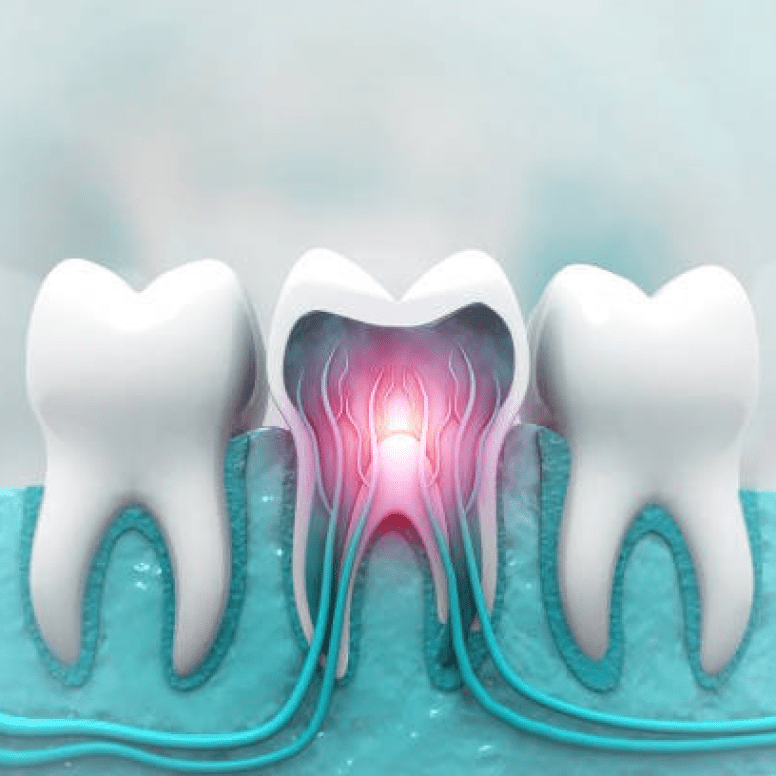

Root Canal

Our high-power microscopes provide extreme precision during Microscopic Root Canal Treatment (RCT). This ensures accurate results and helps save your natural tooth structure.

Yes, you can make an appointment at Dr. Renu Dental Clinic for one-day dentistry Malviya Nagar, where, with modern technology, one-day dentistry can do crowns, root canals, veneers, and smile corrections all in one visit, which saves time and the need for multiple appointments.